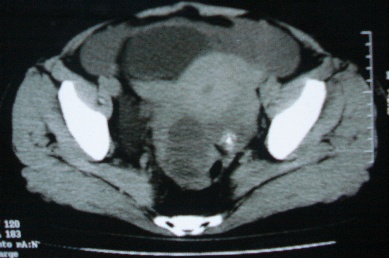

标题: CT8388:女,48岁。感腹胀一周,请会诊

ct10755,女,48岁。感腹胀一周入院。

考虑右侧卵巢囊腺癌并腹腔转移、子宫肌瘤

支持右侧卵巢囊腺癌并腹腔转移

考虑右侧卵巢囊腺癌并腹腔转移可能性大、子宫肌瘤

支持:右侧卵巢囊腺癌并腹腔转移,或囊腺瘤破裂腹腔种植。

支持:右侧卵巢囊腺癌并腹腔转移、腹水、盆腔积液。